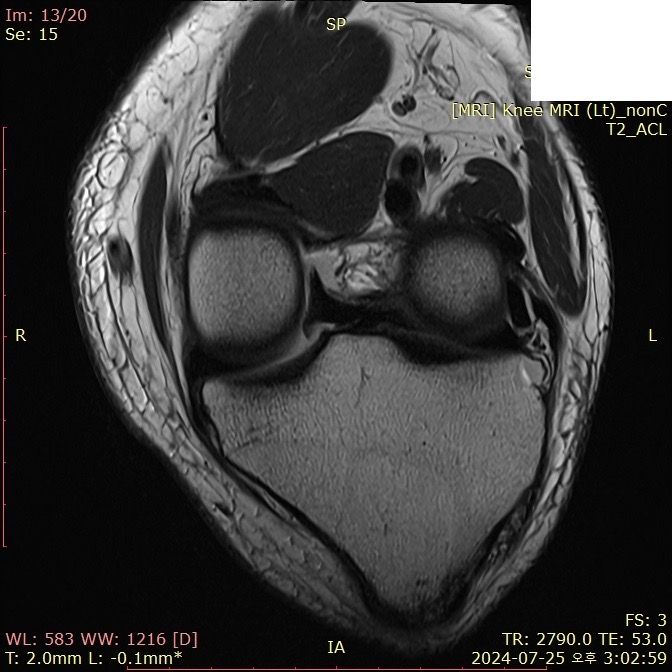

무릎 ACL(전방십자인대) 확인 부탁드려요

아스팔트에 무릎을 부딪쳐 심하게 부어서 mri 찍어봤는데 슬개골 비변위성 골절 판독 받은 건 기억 나는데, 인대는 기억이 잘 안나서 여쭤 봅니다..

전방십자인대 괜찮은가요...??ㅠㅠ